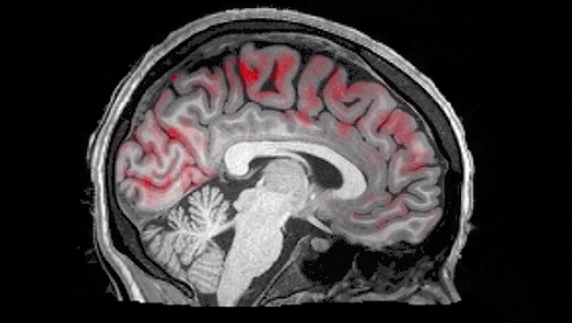

科学家们发现人类在睡着之后,大脑中的血液就会周期性的大量流动,在这个过程中就是一次次的对于大脑进行清洗。科学家们认为这一大股血液就可以把大脑当中的毒素给带出去可以清除老年痴呆症的元凶淀粉样蛋白,所以说科学家才会一直倡导人们睡好,睡饱,可以发现平时睡眠质量比较好的人,大脑会更加清晰,并且记忆力也会更强。

在睡觉的时候,人类的身体也会有很多器官正在工作,并且这也是器官排毒的一个重要方式,身体就可以在睡眠的时候让人类通过呼吸或者是出汗等方式让身体里的赌注全部都一一清除。尤其是大脑可以起到舒缓和排毒的作用,也就是说在感觉十分疲劳的时候,只要睡一个小时或者半个小时,醒来再次开始工作和学习状态就会完全不同。

科学家们倡导大家要给大脑十分充足的清洗和休息的时间,这样就会有更多的精神和更多的活力。避免抽烟,喝酒,还有熬夜,长时间对于大脑的摧残可能就会导致老年时期大脑毒素堆积过多,产生老年痴呆症以及其他的大脑疾病。